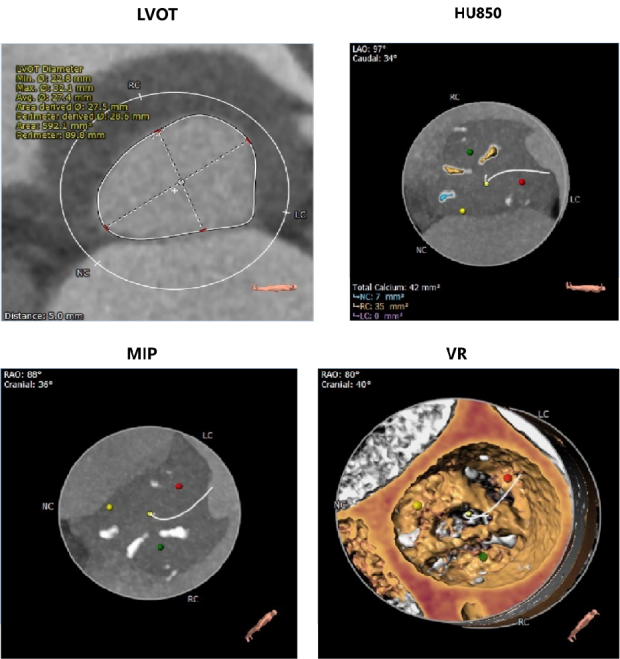

CT数据显示该患者为三叶三窦式主动脉瓣。

左冠开口高度11.0mm,右冠开口高度17.9mm,左冠高度较低,根据瓦氏窦内径和瓣叶长度综合判断,左冠存在一定堵塞风险;左室腔增大,心室壁未见明显增厚。

1、患者主动脉根部钙化分散少量,瓣叶增厚明显,锚定力存在不足;

2、患者左冠开口较低,结合瓦氏窦内结构,存在一定左冠封堵危险;